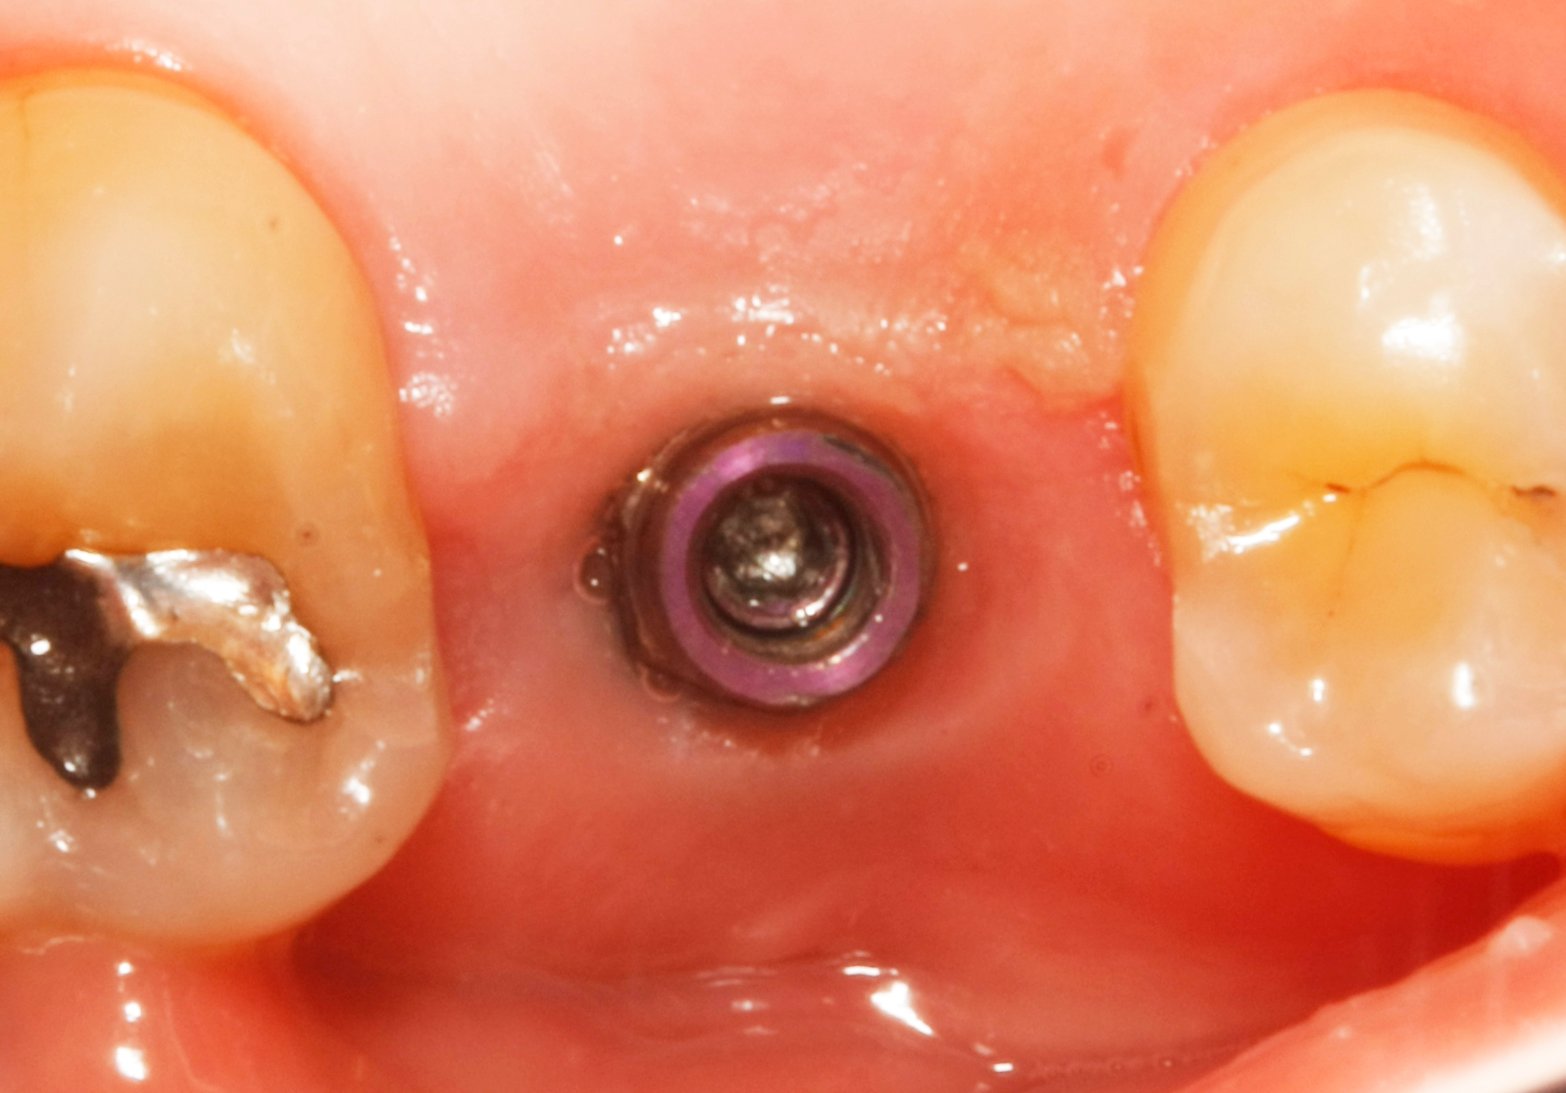

Por favor a ver si alguno sabéis cual es el implante del 12. El paciente se lo colocó en otra clínica y han desaparecido. Conexión interna pero cuadrada (os mando [...]